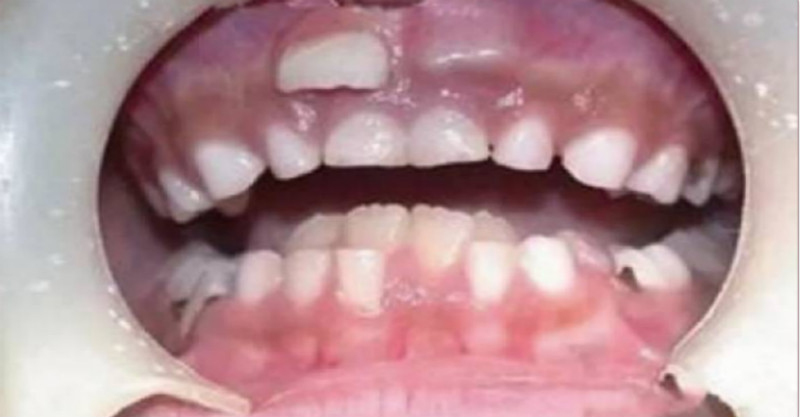

「8歲男孩長了雙排牙」

兒子上一年級後,班上其他同學都開始換牙了,他卻一直沒動靜,直到8歲他才開始出現換牙跡象。由於舊的乳牙沒有及時脫落,下牙齒中間長出的兩顆新牙被擠成倒八字的形狀生長,中間還產生了半個牙的空隙,乍看上去就像兩排異形的牙,就是「雙排牙」!

一般情況下,孩子6、7歲時,乳牙就完成使命,自動脫落,隨後恆牙逐漸萌出,成為孩子一輩子的好夥伴。但是,有些孩子恆牙已經長出來了,而相應的乳牙卻不肯「退位讓賢」,恆牙被迫從乳牙後麵「委曲求全」,從而形成一前一後兩層牙齒。

由於舊的乳牙沒有及時脫落,下牙齒中間長出的兩顆新牙被擠成倒八字的形狀生長,中間還產生了半個牙的空隙,乍看上去就像兩排異形的牙,就是「雙排牙」!